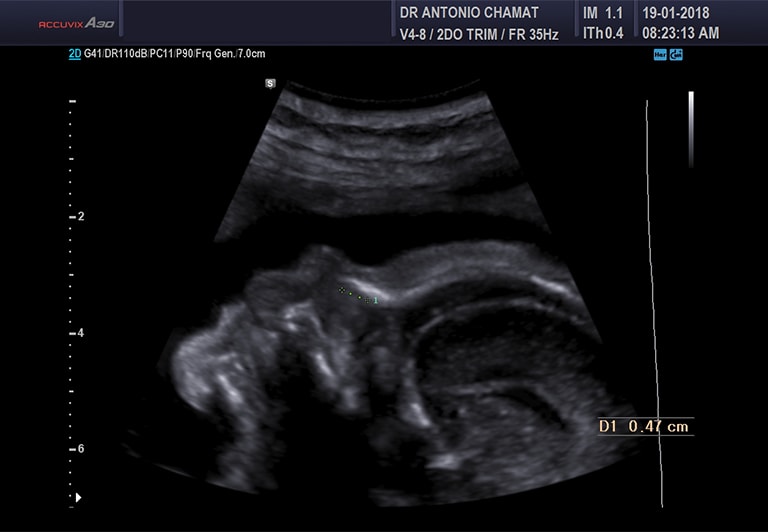

Ecografía Obstétrica

Esta se puede realizar desde el primer trimestre de embarazo y permite, con una sola medida, calcular la edad gestacional. Se realiza principalmente por vía transvaginal y en algunos casos es posible hacerla por vía abdominal. Es una ecografía básica en la cual se informa la posición fetal, se toman las medidas de biometría y peso y se revisa el estado de los anexos ovulares (cordón umbilical, líquido amniótico y placenta).